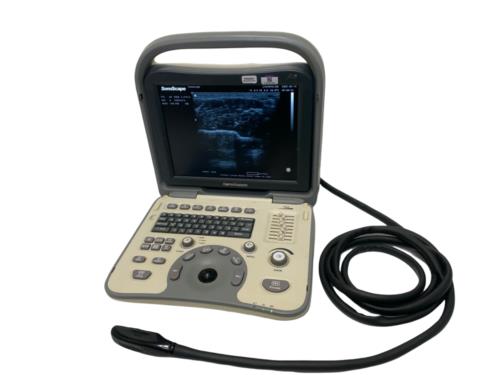

DIAGNOSTIC ULTRASOUND MACHINES FOR SALE

Mindray M9 Portable Ultrasound With 2 Probes

Sale price$ 22,302.88